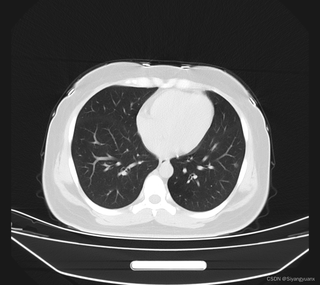

我们输入的png图片长这样: